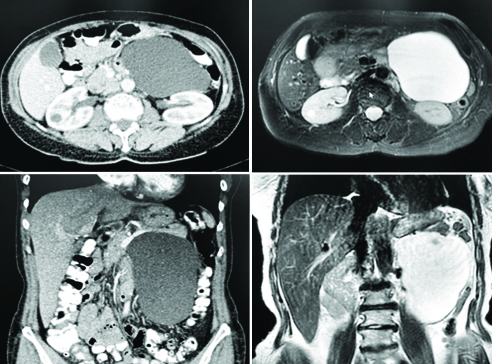

A 59-year old Caucasian female patient presented to our surgical admissions unit with vague abdominal pain, abdominal distension and progressive constipation, with dependence on laxatives. Her past medical history was unremarkable and she had no previous abdominal or pelvic surgery. Clinical examination revealed a moderately distended abdomen, with palpable fullness in the left upper quadrant of the abdomen, as well as the left hypogastrium. Her admission blood tests were within normal range. Of note, the patient had been investigated with a flexible sigmoidoscopy, as well as completion colonoscopy, due to her altered bowel habits, which reported a non-critical segmental narrowing proximally to the sigmoid colon. The patient was scheduled for a computed tomography (CT) and subsequently magnetic resonance (MR) scans of her abdomen and pelvis, which revealed the presence of a large 14.5x14.0x5.5 cm, probably cystic, lesion of the left-sided colonic mesentery, splaying the inferior mesenteric vessels, as well as the pancreatic tail (figs. 1, 2).

Figure 1 - Compilation of the preoperative CT & MR images, demonstrating the presence of fluid-filled cystic lesion, arising from the mesentery of the descending colon and displacing the pancreatic tail in cephalad position